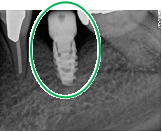

【インプラント埋入前】

冠はブリッジを切断しただけで取れてきました。軟化象牙質を取り除いたところ、歯根しか残っていない状況で保存できるかどうかのぎりぎりのところでした。